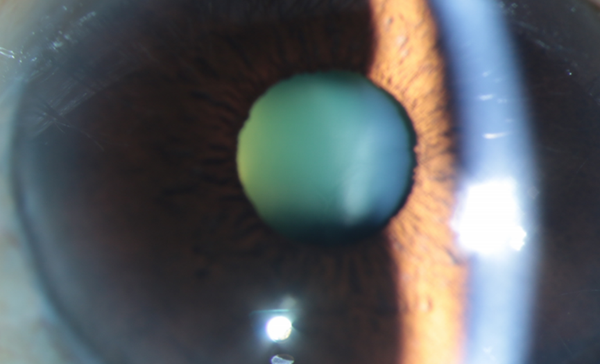

更令人揪心的是,不久前邓阿姨赖以视物的右眼出现白内障,日常生活和行动都受到了极大限制。

随着白内障逐渐加重,邓阿姨在家人的陪伴下,到郑州爱尔眼科医院,找到了白内障与老视专科 冯珂主任。

仔细检查后,冯珂发现邓阿姨的情况确实复杂:左眼手动视力几乎无法提升,右眼白内障又影响了仅存的视力来源,需要尽快手术治疗恢复视力。

冯珂利用先进的“飞秒激光的辅助白内障手术”技术,精确地在角膜上制作微切口,然后利用激光进行前囊膜切开和晶状体预劈核。

飞秒激光白内障手术是眼科领域的一项革命性技术。打破了传统白内障手术中,医生需要手工制作切口、撕囊和劈核,精度达到微米级别,大大提高对于“单眼”的邓阿姨手术的安全性和可预测性。